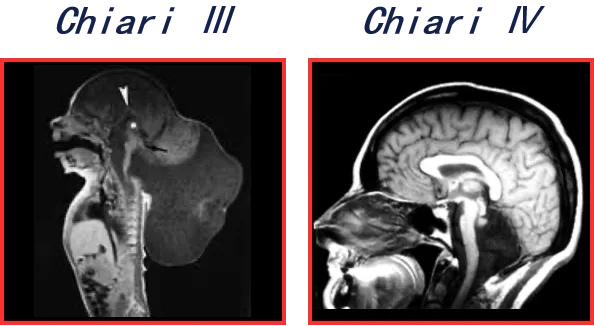

▶▷Chiari III型(CIM-III):罕见的一种,主要表现为小脑组织由枕骨大孔向枕后膨出,严重者甚至可包括脑干及脑实质部分组织。

▶▷Chiari IV型(CIM-IV):分叶良好的小脑发育不良,可合并小脑幕狭窄或后颅窝、枕大孔狭小等表现。